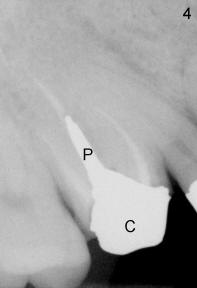

1. A post is needed when the tooth has a large defect and has finished root canal therapy (R in Fig.1).  There are two types of post: prefabricated and cast (one and two appointments, for small and large decays, respectively).  A post space is created in the largest canal of the tooth (arrowheads in Fig.2).  Either a prefabricated post is inserted into the post space or a plastic pattern is made to fit the space.  The outside portion of the pattern is prepared (trimmed) to become part of the tooth structure.  The plastic pattern is sent to lab to make a cast post (P) and core (C, Fig.3), which is inserted (Fig.4) into the post space.  Finally a crown is cemented (Cr in Fig.5)

3. PA device is needed for both appointments: to confirm length of post space to be created (Fig.2) and seating of cast post (Fig.4)